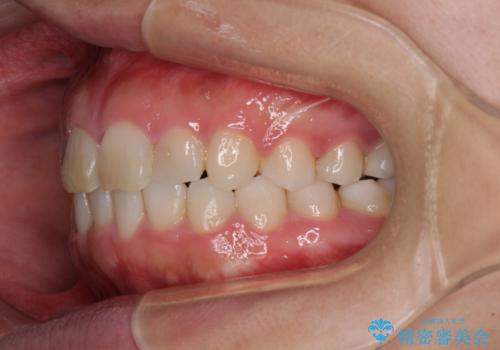

- ワイヤーではない矯正治療があると聞いたとのことで来院された患者様です。

長年前歯のデコボコを気にしていたもののワイヤー矯正に抵抗があり躊躇していたそうですが、インビザラインなら治療してみたいとのことで相談にいらっしゃいました。

インビザライン適用の歯列であったため、歯と歯の間を削るIPRを用いて改善することとしました。

お仕事柄、長時間のマウスピース装着が苦ではなかったので、歯列はすぐに整いましたが、ゆっくりとした交換頻度であったので、2年ほどの治療期間を要しました。